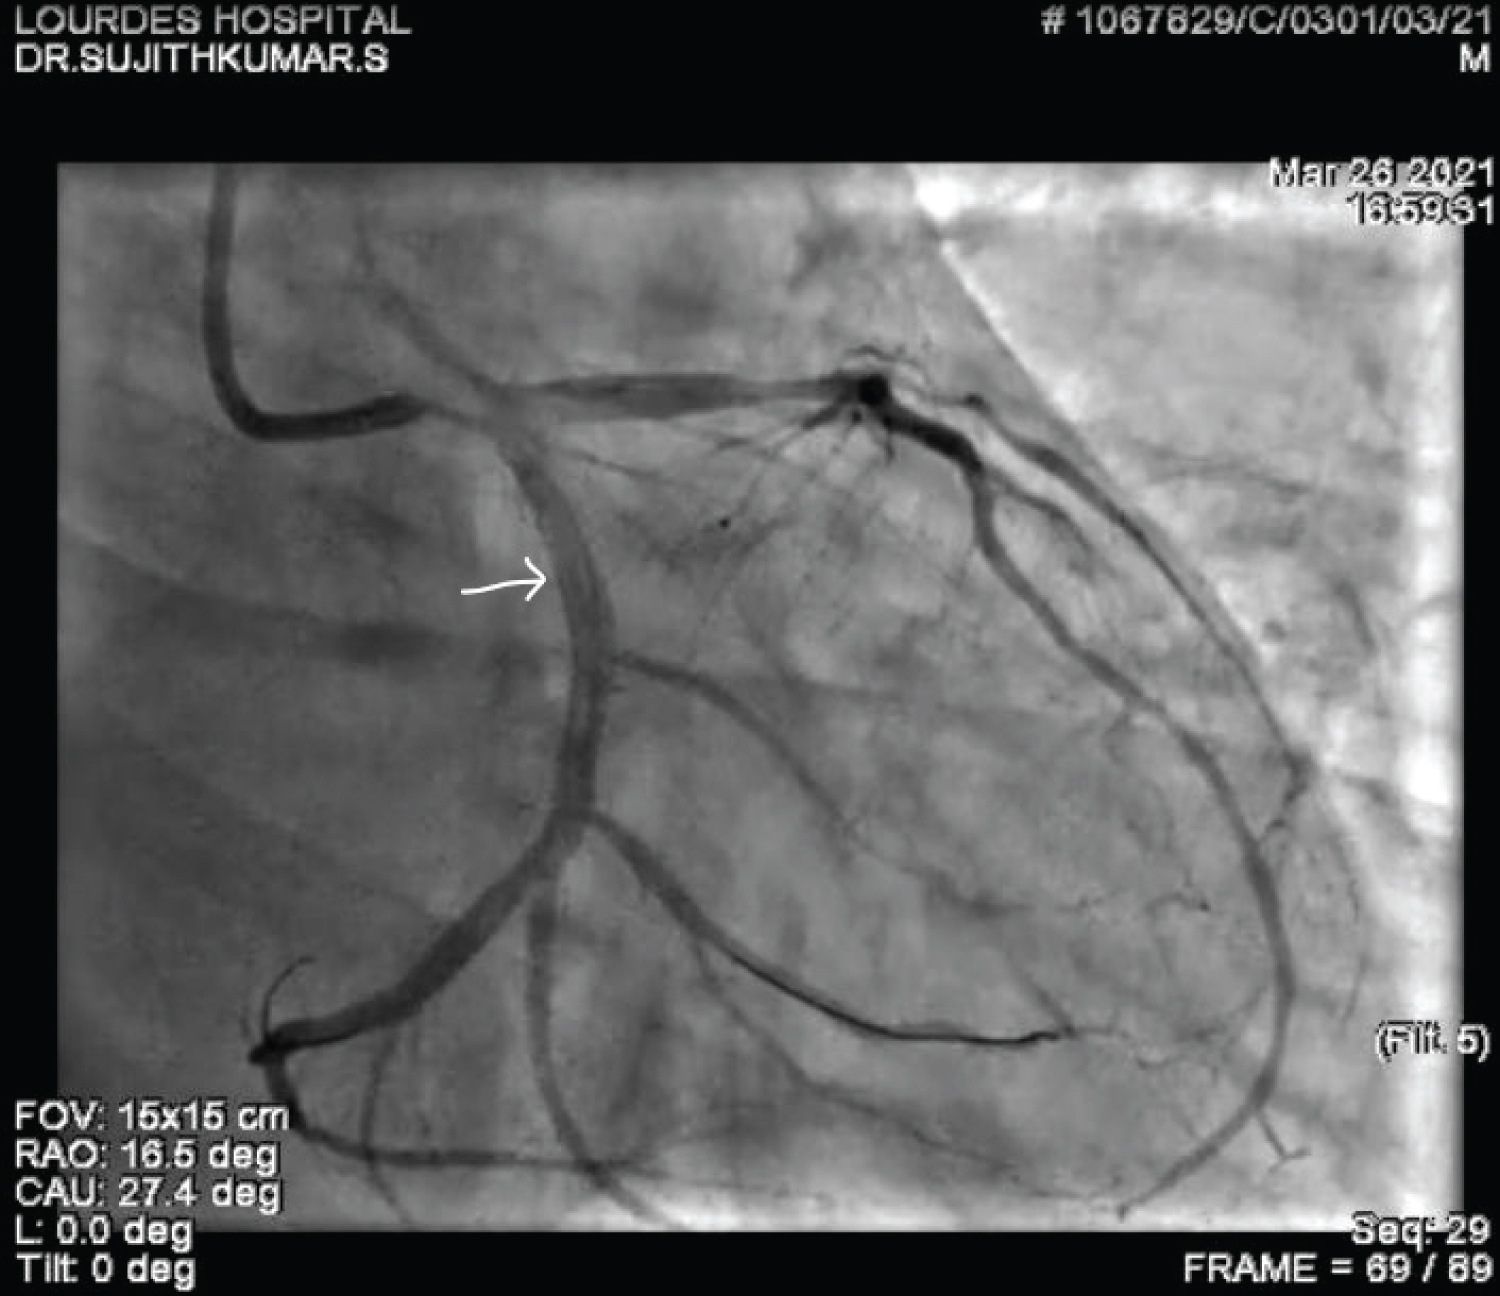

A 60-year-old gentleman was referred to our care with a diagnosis of Inferior Wall Myocardial Infarction, after receiving thrombolytic therapy at a local hospital. ECG, at admission, showed good ST resolution. He was taken up for elective coronary angiogram and revascularization. Coronary angiogram revealed a critical stenosis of dominant Left Circumflex artery (LCX) at Obtuse Marginal artery (OM2) (medina 1,0,1) with TIMI II flow distally (Figure 1 and Video 1). He underwent angioplasty and stenting with a single stent strategy. The LCX was predilated and was stented with a 3 × 24 mm Biomime stent at 14 atmospheres (Figure 2, Figure 3, Figure 4, Video 2 and Video 3). The OM2 was rewired and a dilatation of the ostial lesion of OM2 and kissing balloon inflation was done with excellent result. It was decided to do proximal optimization (POT) to the proximal stent with a 3.25 × 8 mm non-compliant (NC) balloon. But there was difficulty in tracking the balloon down into the stent and fluoroscopy showed a deformation of the proximal edge of the stent which was confirmed by the Stent Viz technology (Figure 5, Figure 6, Figure 7, Video 2 and Video 3). The same NC balloon was then used to post-dilate the stent and the proximal part of the stent was covered with another 3.5 × 13 mm biomime stent with excellent result (Figure 8). After 4 months follow up, the patient is asymptomatic and on dual antiplatelets.

Figure 8: Final coronary angiogram in RAO caudal projection after the deployment of the second stent proximally. View Figure 8